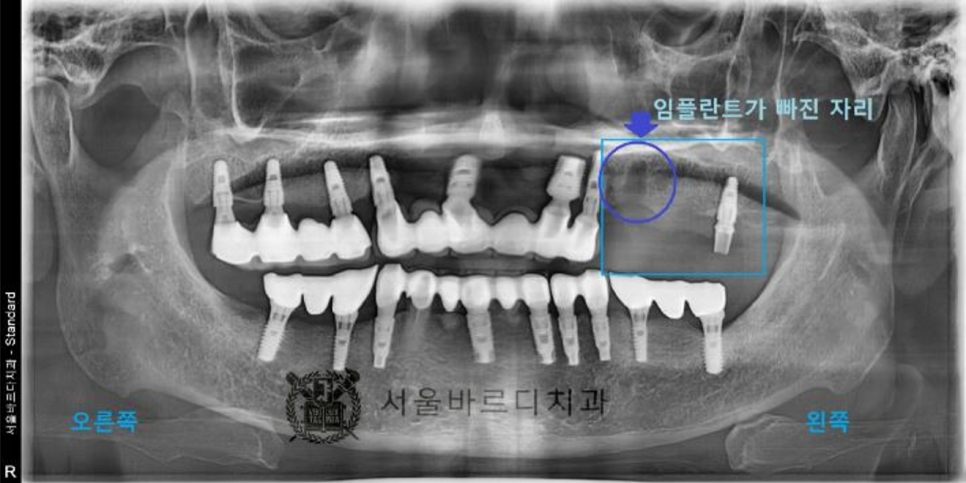

파노라마 엑스레이 촬영 후 검사 결과 전체적으로

잇몸이 많이 내려가신 상태이고

안 좋은 곳들이 많이 있었고,

20년 전에 치료하신 치아들이라 보철물도

여기 저기 많이 깨져있었습니다.

그 중에서 환자분께서는

왼쪽 아래 임플란트 치료를 우선적으로 원하셨습니다

왼쪽 아래 부분의 임플란트 브릿지는 많이 흔들려서

음식을 드실 수 없는 상태이셨습니다.

몇 달 후 이 환자분께서 왼쪽 위 임플란트가 빠져서 다시 내원하셨습니다.

20230414

20230620

임플란트 2개로 4개의 치아를 만들어 놓은 브릿지인데…

사진상으로도 뼈소실이 많이 있었고,

심하게 흔들리는 상태이셨는데 자연적으로 빠지셨습니다.

앞에 임플란트(작은 어금니)의 뿌리 부분의 뼈가 염증으로 녹아

더 이상 임플란트가 뼈에 박혀 있을 수 없어서

뒤 보철물과 함께 빠진 경우입니다.

그나마 끝 어금니(큰어금니)가 잡아주고 있어서

지금까지 사용이 가능했으나

끝 어금니 임플란트의 나사가 풀리면서

보철물이 빠지게 된 것입니다..

아직 임플란트가 빠진 흔적이 잇몸에 남아 있습니다.